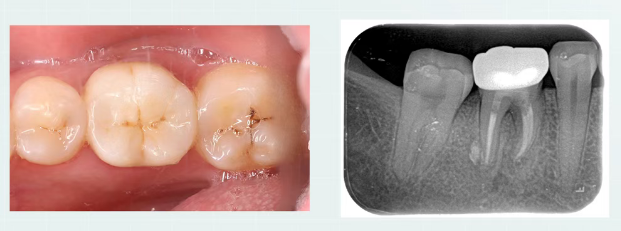

2个月复查

治疗后两月完成最终修复,临床检查无症状,行使功能良好;通过根尖片可见根尖低密度暗影有改善,根分叉处及牙周膜增宽影像呈现愈合趋势;

除了糊剂些许溢出外,一切良好,得益于nRootSP良好的性能。

8个月复查

治疗术后八月复查,糊剂固化稳定,

根分叉处及牙周膜影像较术后两月有明显改变。